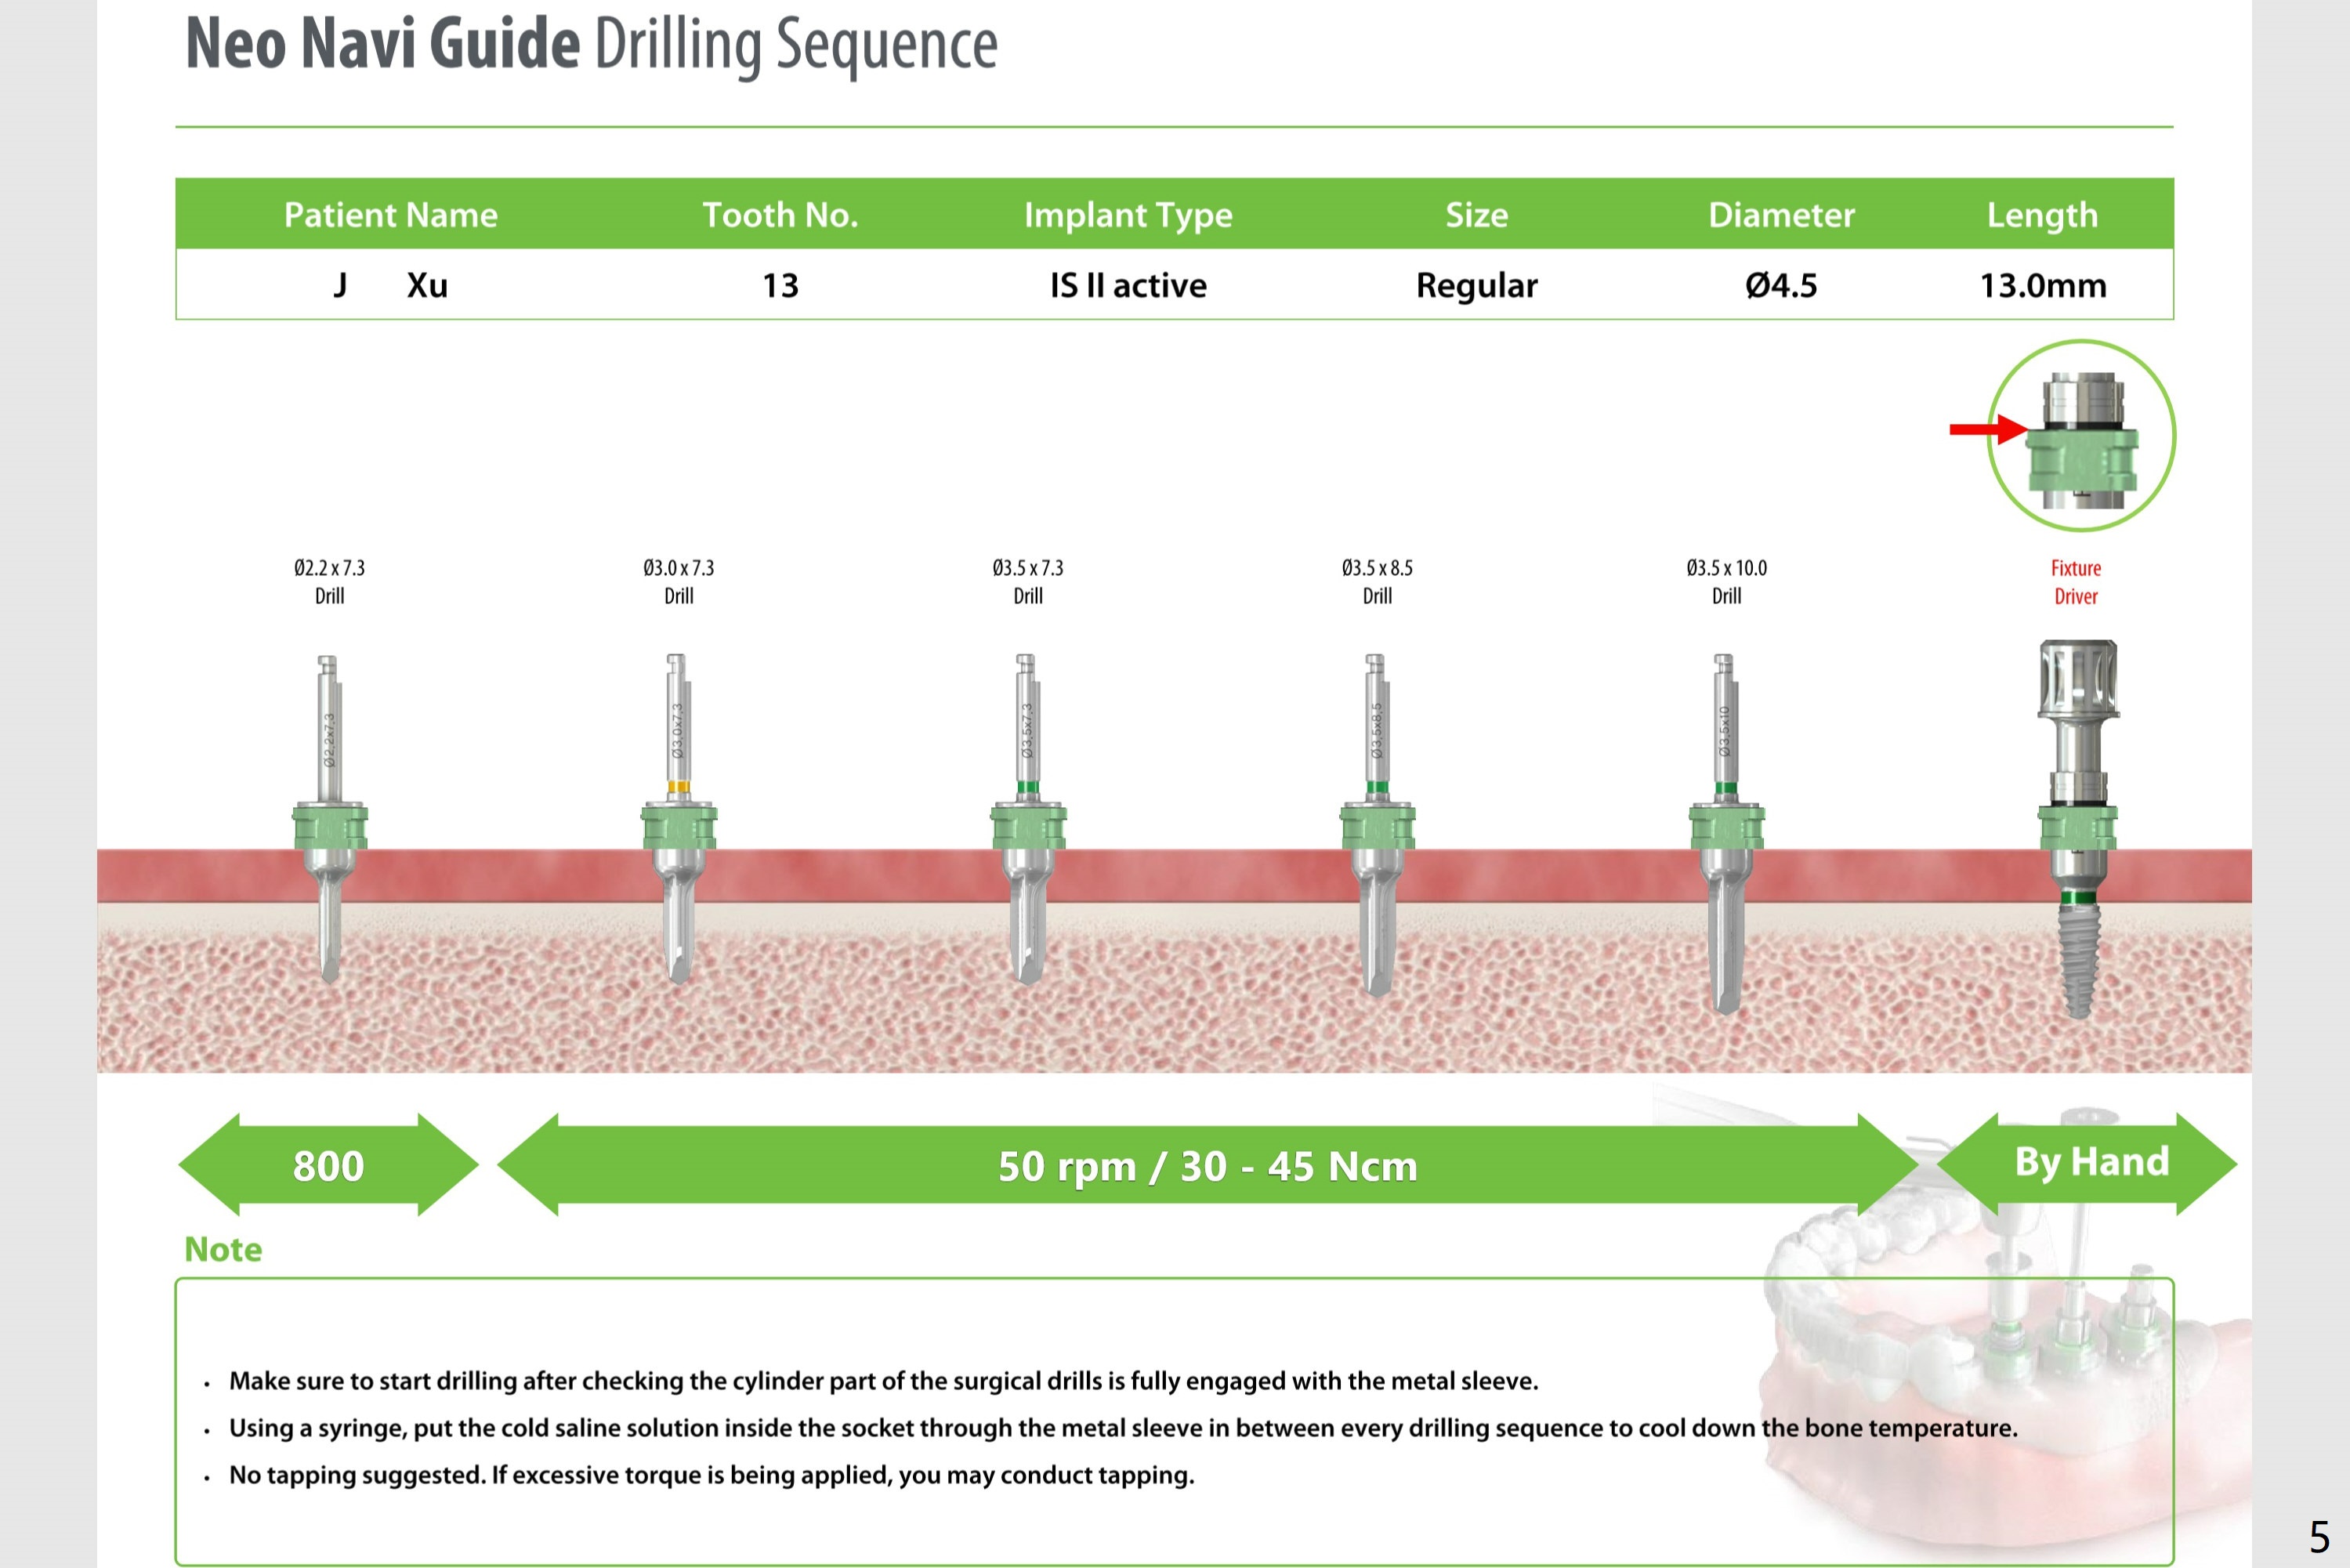

After #13 implant placement, remove DO caries at #14 for composite and splinted provisional. Consider taking PA after 2.2 mm drill to depth because of the curved root of #12. Placee IBS implant with IS driver.